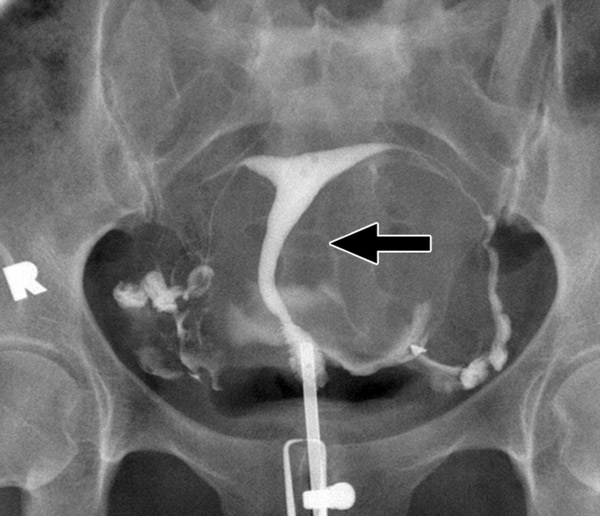

Медицинские снимки: Проходимость маточных труб